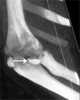

Fracture fragment

A Smith's fracture, is a fracture of the distal radius. It is caused by a direct blow to the dorsal forearm or falling onto flexed wrists, as opposed to a Colles' fracture which occurs as a result of falling onto wrists in extension. [Source: Wikipedia ]